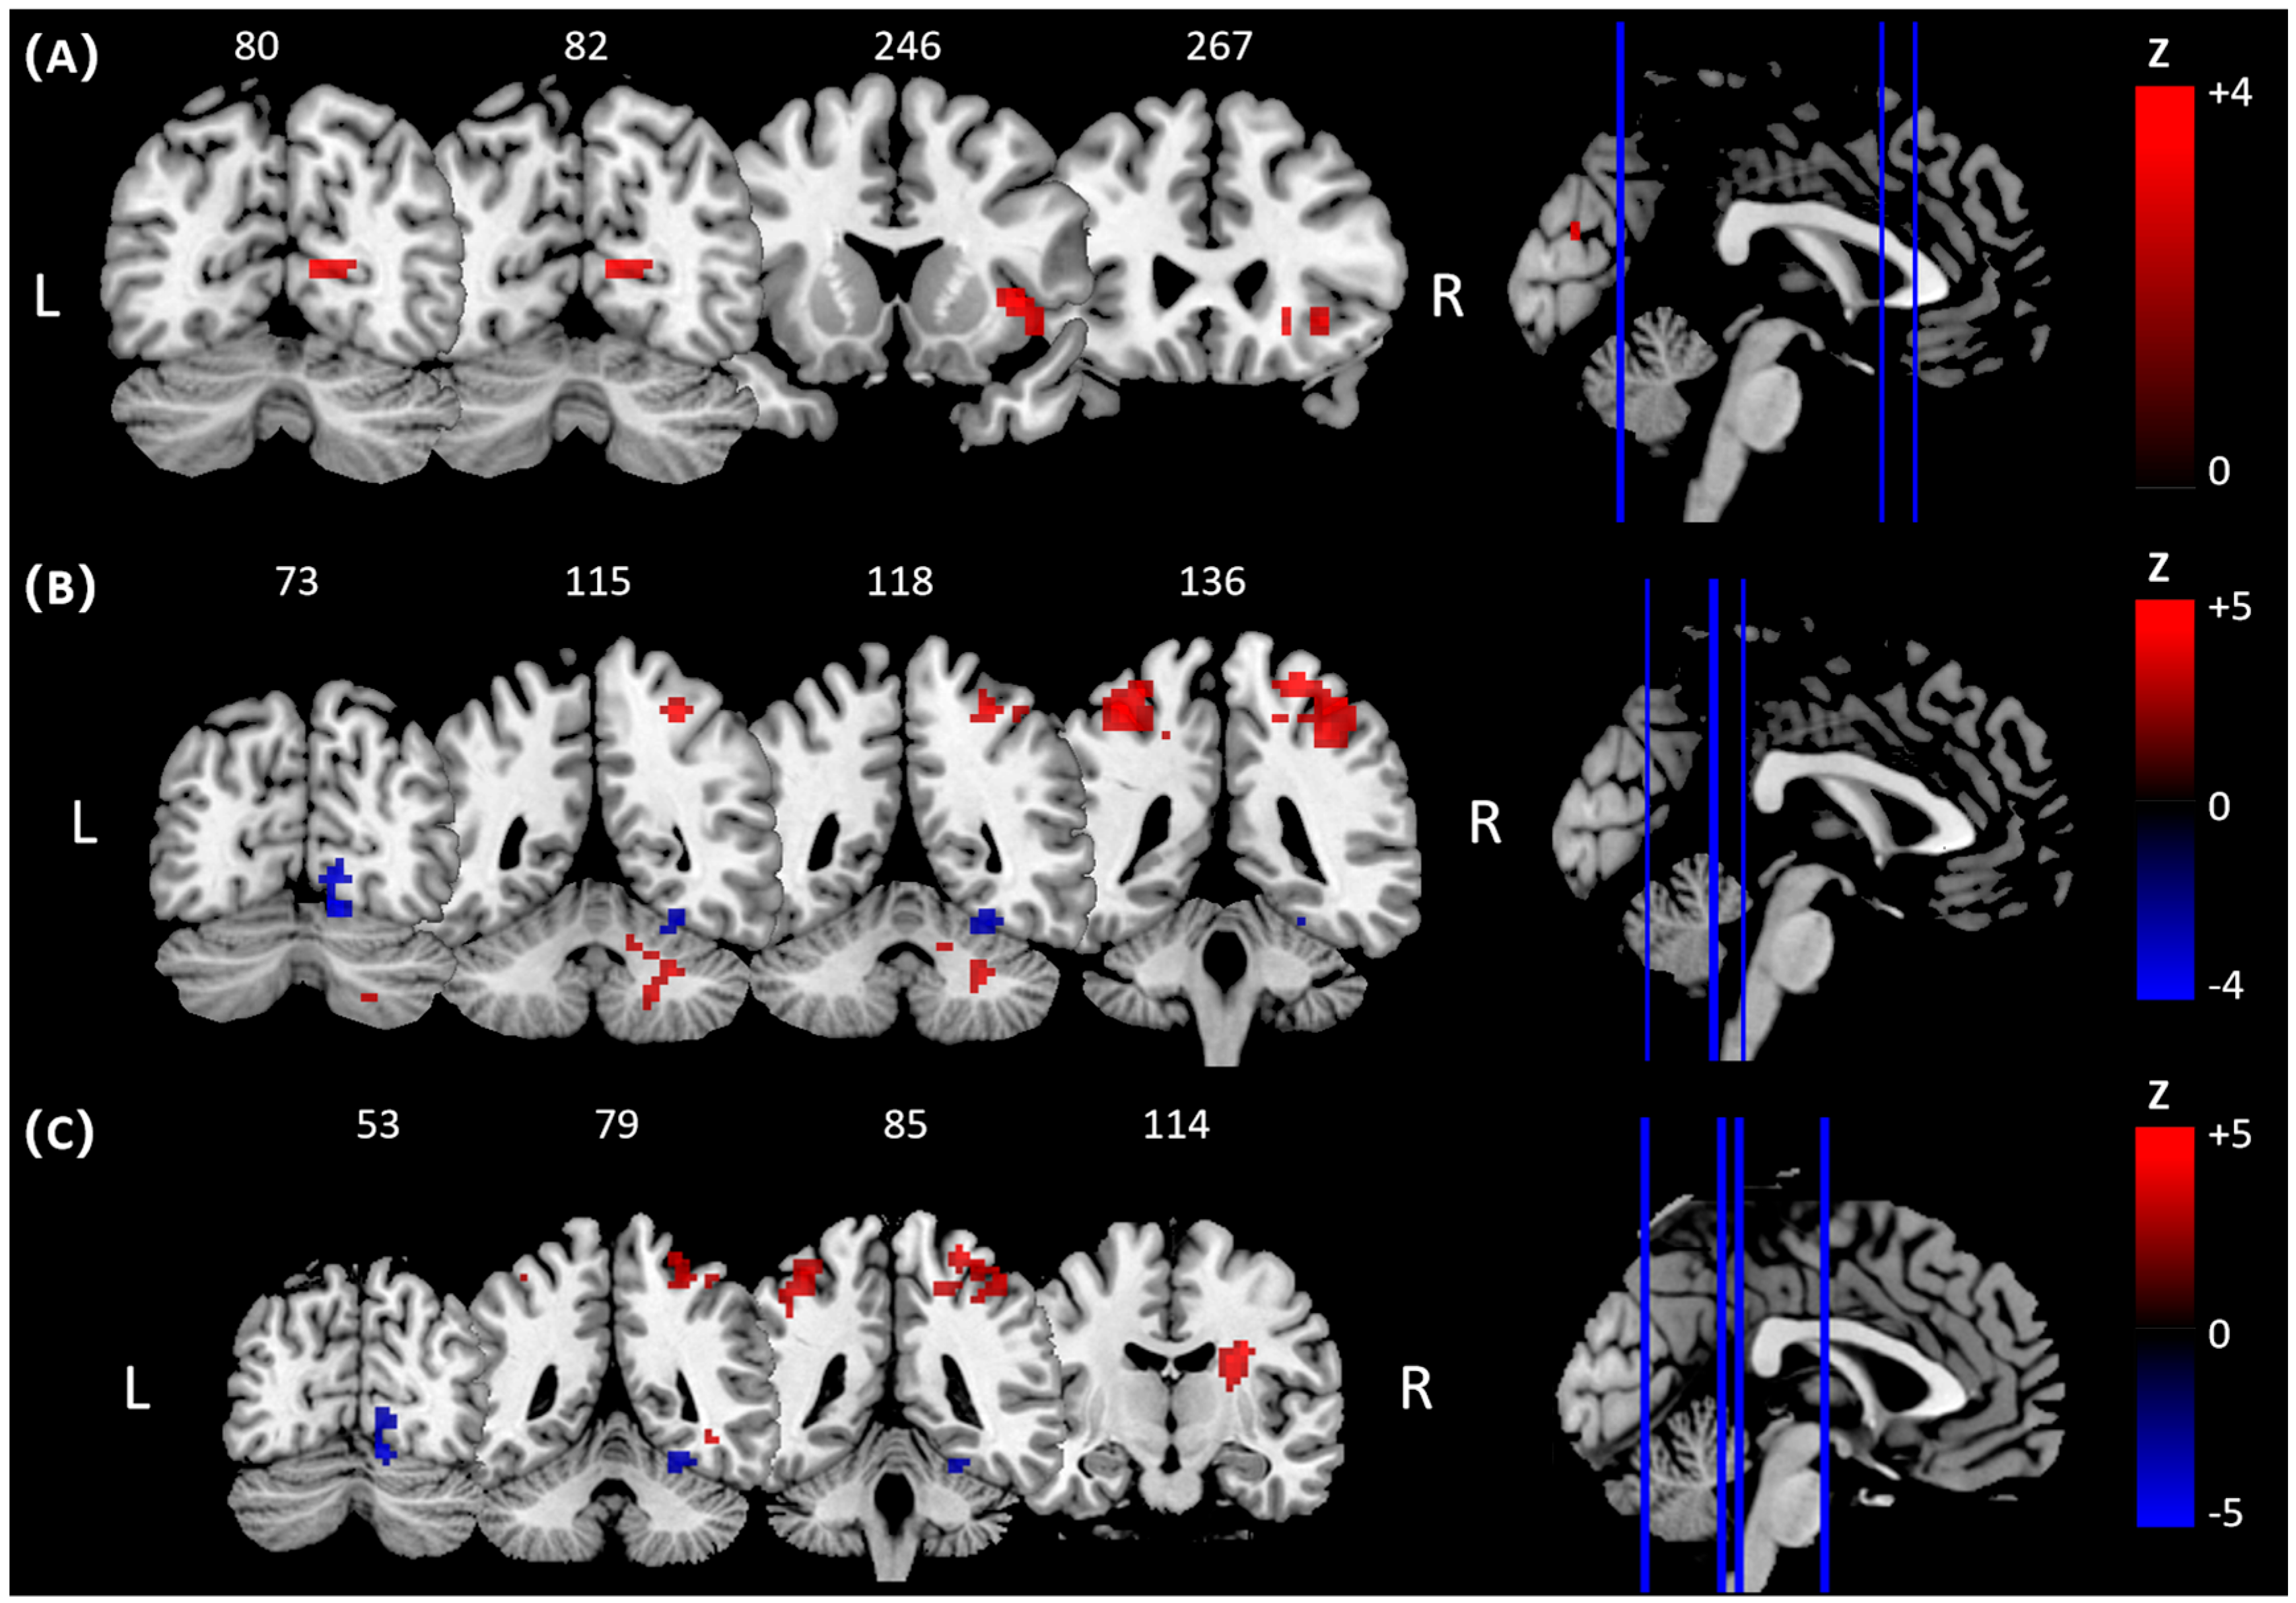

| Comparisons | Brain Regions/BA | Peak MNI Coordinates | Cluster Voxels | Peak Z Values | |||

|---|---|---|---|---|---|---|---|

| x | y | z | |||||

| Pre-hitting | Golf group > Control group | R Insula/BA 48 | 39 | 15 | 0 | 67 | 3.90 a |

| R Posterior Cingulate Cortex (PCC)/BA 17 | 18 | −60 | 12 | 69 | 3.85 a | ||

| Hitting | Golf group > Control group | R Cerebelum/BA 19 | 18 | −57 | −27 | 99 | 4.36 a |

| L Postcentral Gyrus/BA 2 | −36 | −39 | 57 | 105 | 4.26 a | ||

| R Postcentral Gyrus/BA 2 | 27 | −39 | 66 | 255 | 4.04 a | ||

| Golf group < Control group | R Cerebellum/BA 18 | 12 | −72 | −15 | 114 | 4.05 a | |

| Hitting > Pre-hitting | Golf group < Control group | L Postcentral Gyrus/BA 2 | −36 | −39 | 57 | 175 | 4.54 a |

| R Postcentral Gyrus/BA 4 | 33 | −33 | 66 | 199 | 4.06 a | ||